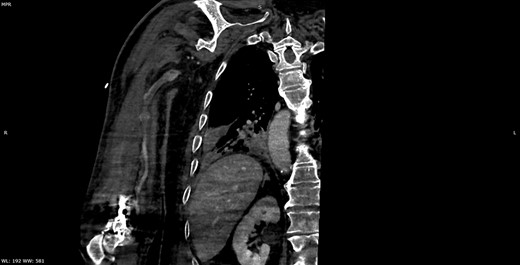

Seven days later, while his general condition was deteriorating, he developed acute ischemia in his right thumb and index finger (Fig. 2). In the ipsilateral forearm, a radial artery catheter had been inserted for monitoring. An urgent radial artery embolectomy was performed and restored the arterial supply to the right hand. The antithrombotic agent was changed to fondaparinux (7.5 mg/once daily). However, within the next few days, it was clinically evident that the revascularization effort was unsuccessful as the thumb and index finger developed dry gangrene. On examination, there was no palpable radial pulse, the ulnar artery pulse was palpable at the level of the wrist and the capillary refill time was normal at the middle, ring and little fingers. A CT angiography (Figs 3 and 4) was performed, demonstrating complete thrombosis of the radial artery beginning at the level of the elbow as well as a 70% occlusion of the ulnar artery ~15 cm proximal to the wrist. Thrombosis of the right axillary vein was also seen (Fig. 5). Orthopedic review was requested for consideration for finger amputation with a recommendation for arm amputation at the level of the elbow. Unfortunately, the patient died 72 h later from respiratory failure following a 24-day admission in ICU.

Multiplanar reformation image shows filling defect in the right axillary vein consistent with thrombosis.